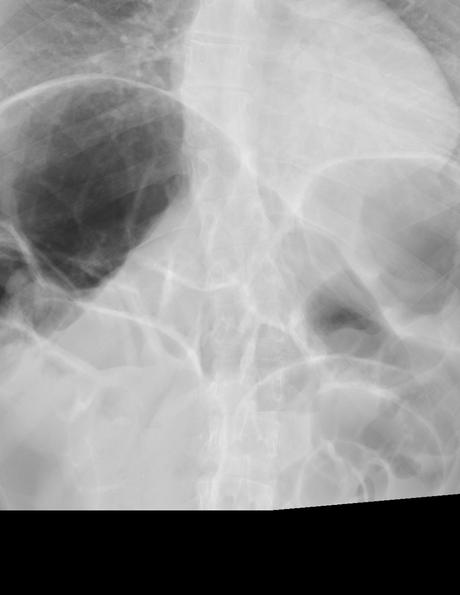

Se realizó estudio radiográfico de tórax, en proyección anteroposterior, observando lo siguiente:

Se logra identificar marcada dilatación de las asas de intestino delgado y colon. El colon transverso presenta un calibre de hasta 76 mm.

Impresión diagnóstica:

Estudio radiográfico de tórax que muestra severa dilatación de las asas intestinales. Se sugiere complementar con estudios adicionales.